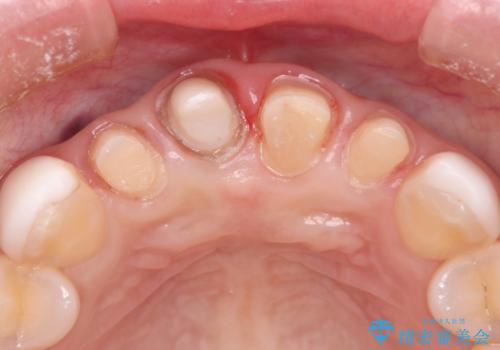

- 他院で治療した前歯の色が気になるということで来院された患者様です。前歯に色の差があり、レントゲンから内部にう蝕も見られたため、審美性に優れ、う蝕になりにくいオールセラミッククラウンで治療いたしました。